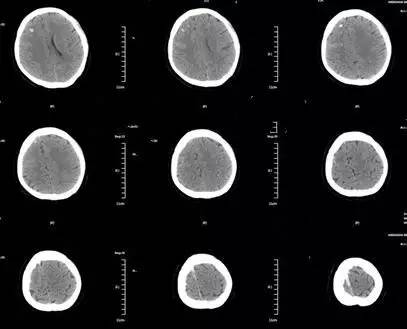

基本信息:患者女性,24岁。产后第3天,因“突发四肢抽搐4小时。” 2016-03-09入院。神志嗜睡状,GCS评分3+5+6=14分,四肢肌力V级。

▼头颅CT如下。

▼头颅CTV。

▼头颅MRV。

诊治经过:予口服华法林现PT-INR:2.45,现门诊复查随访。